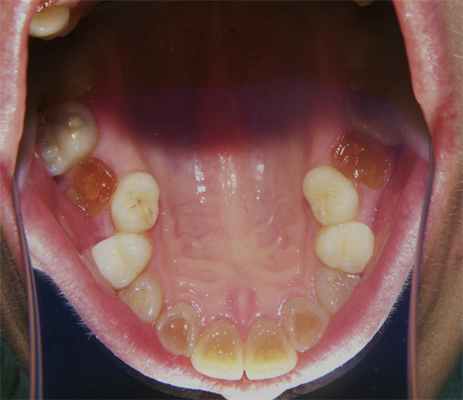

Общие сведения из анамнеза двух сестер: молочные зубы были серые, полупрозрачные и очень хрупкие. Наблюдалась задержка физиологической резорбции корней, поэтому молочные зубы удалялись. Кариесом временные зубы не поражались и никогда не болели. Постоянные зубы прорезались в нормальные сроки, но сразу же имели серый цвет и прозрачность (рис. 1а).

Рис. 1а. Зубы младшей сестры.

Уже в младшем школьном возрасте коронки постоянных зубов начали скалываться от физиологической нагрузки, в первую очередь шестые зубы. Границы сколов проходили по глубоким слоям дентина (рис. 2).

Дефекты коронок многократно пломбировались, но безуспешно. Пломбы выпадали быстро, иногда через несколько часов. У младшей сестры в 15—16-летнем возрасте были удалены четыре зуба из-за полного их разрушения. При клиническом исследовании установлено, что симптомы заболевания у сестер аналогичны, однако более выраженны у младшей сестры. Зубы имеют необычный цвет, но окраска зубов неоднородная. Цвет колеблется от серого до светло-коричневого с янтарной полупрозрачностью. У младшей сестры зубы окрашены более интенсивно, и здоровый вид у нее имеют только восьмые зубы. У старшей сестры нормальный цвет имеют верхние премоляры, а также сохранившиеся моляры (рис. 1б).

У обеих сестер более интенсивно окрашены зубы нижней челюсти. У старшей сестры зубы более крупные и имеют бочкообразную форму, у младшей бочкообразность зубов менее выраженна. Все зубы устойчивы. Имеются множественные сколы зубов. Края сколов находятся под десной, а линии сколов проходят по предполагаемым границам полостей зубов. Полости зубов облитерированы. Все участки обнаженного дентина имеют коричневый цвет, тверды и безболезненны при зондировании (рис. 3).